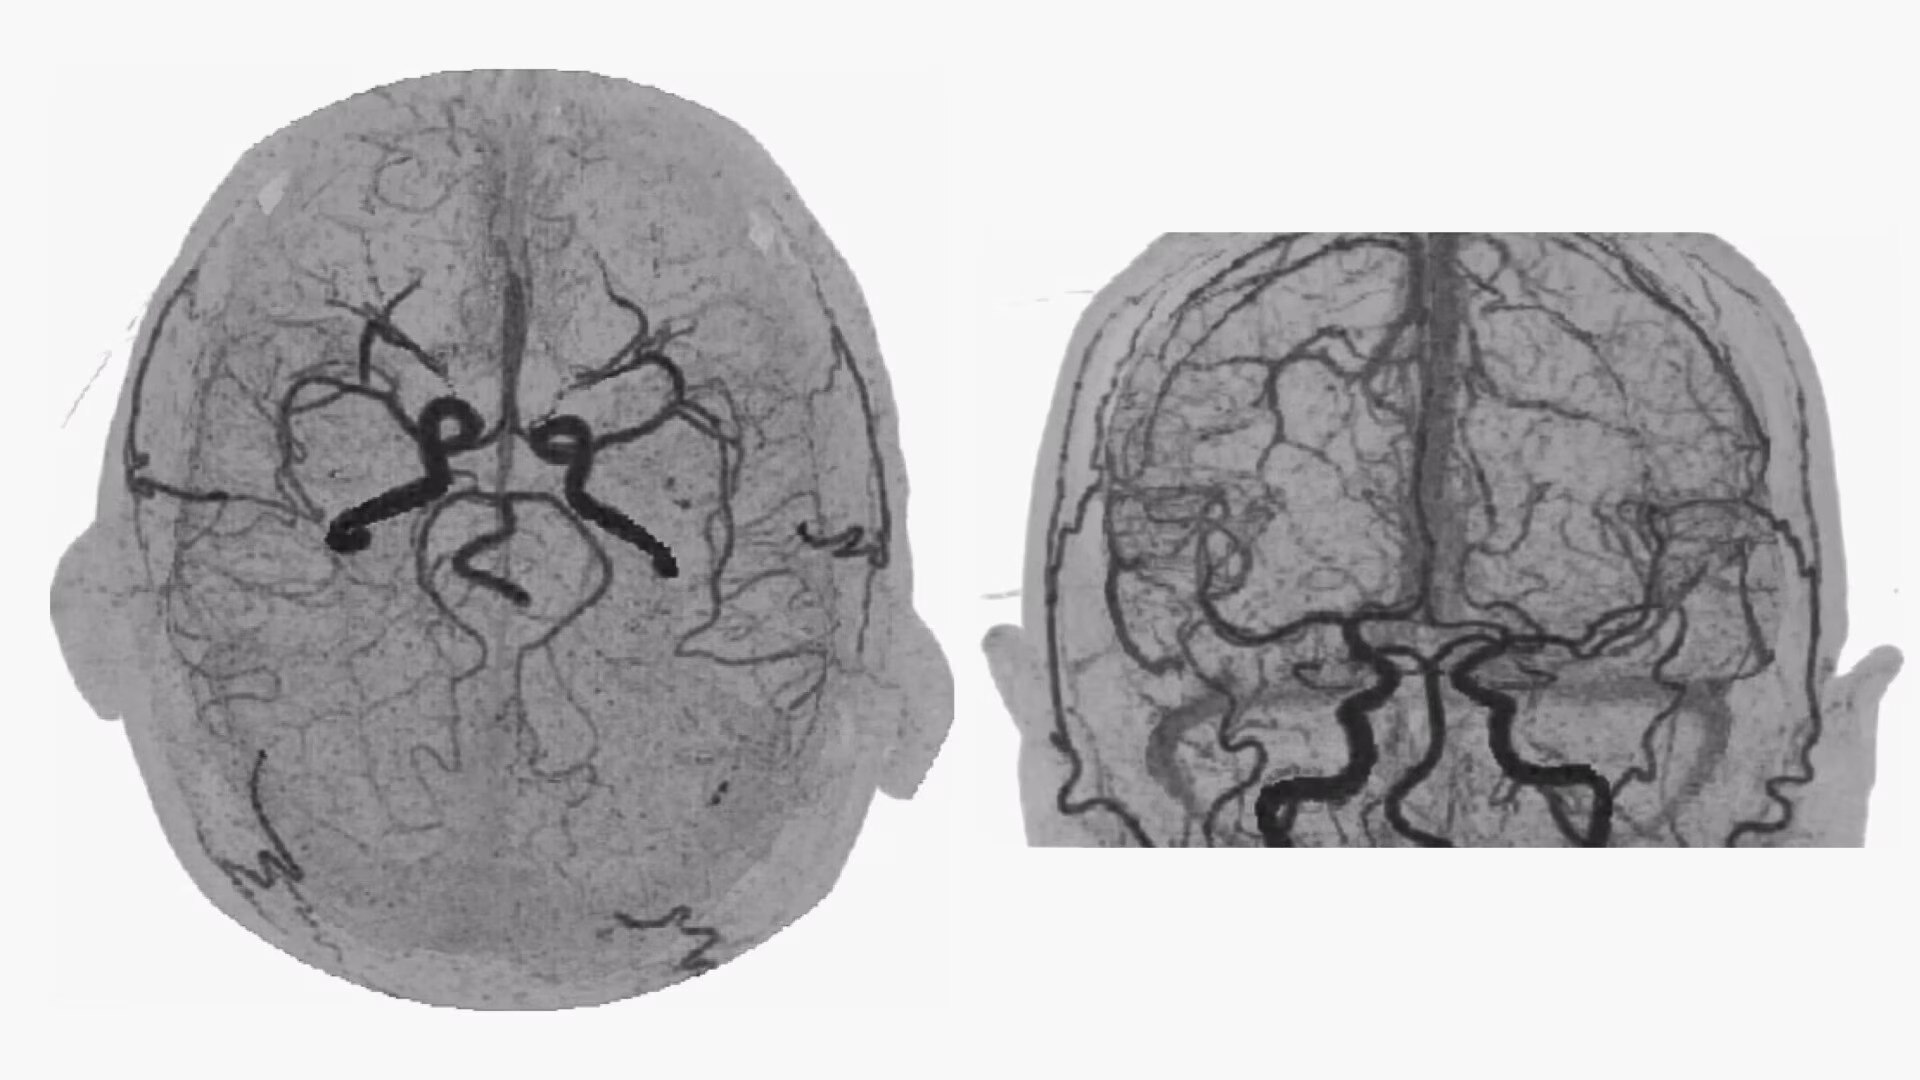

Dynamic Shuttle

Bone-free dynamic visualization of vascular anatomy.

• 4D Neuro Digital Subtraction angiography (DSA) automatically performs image registration, then removes bone.